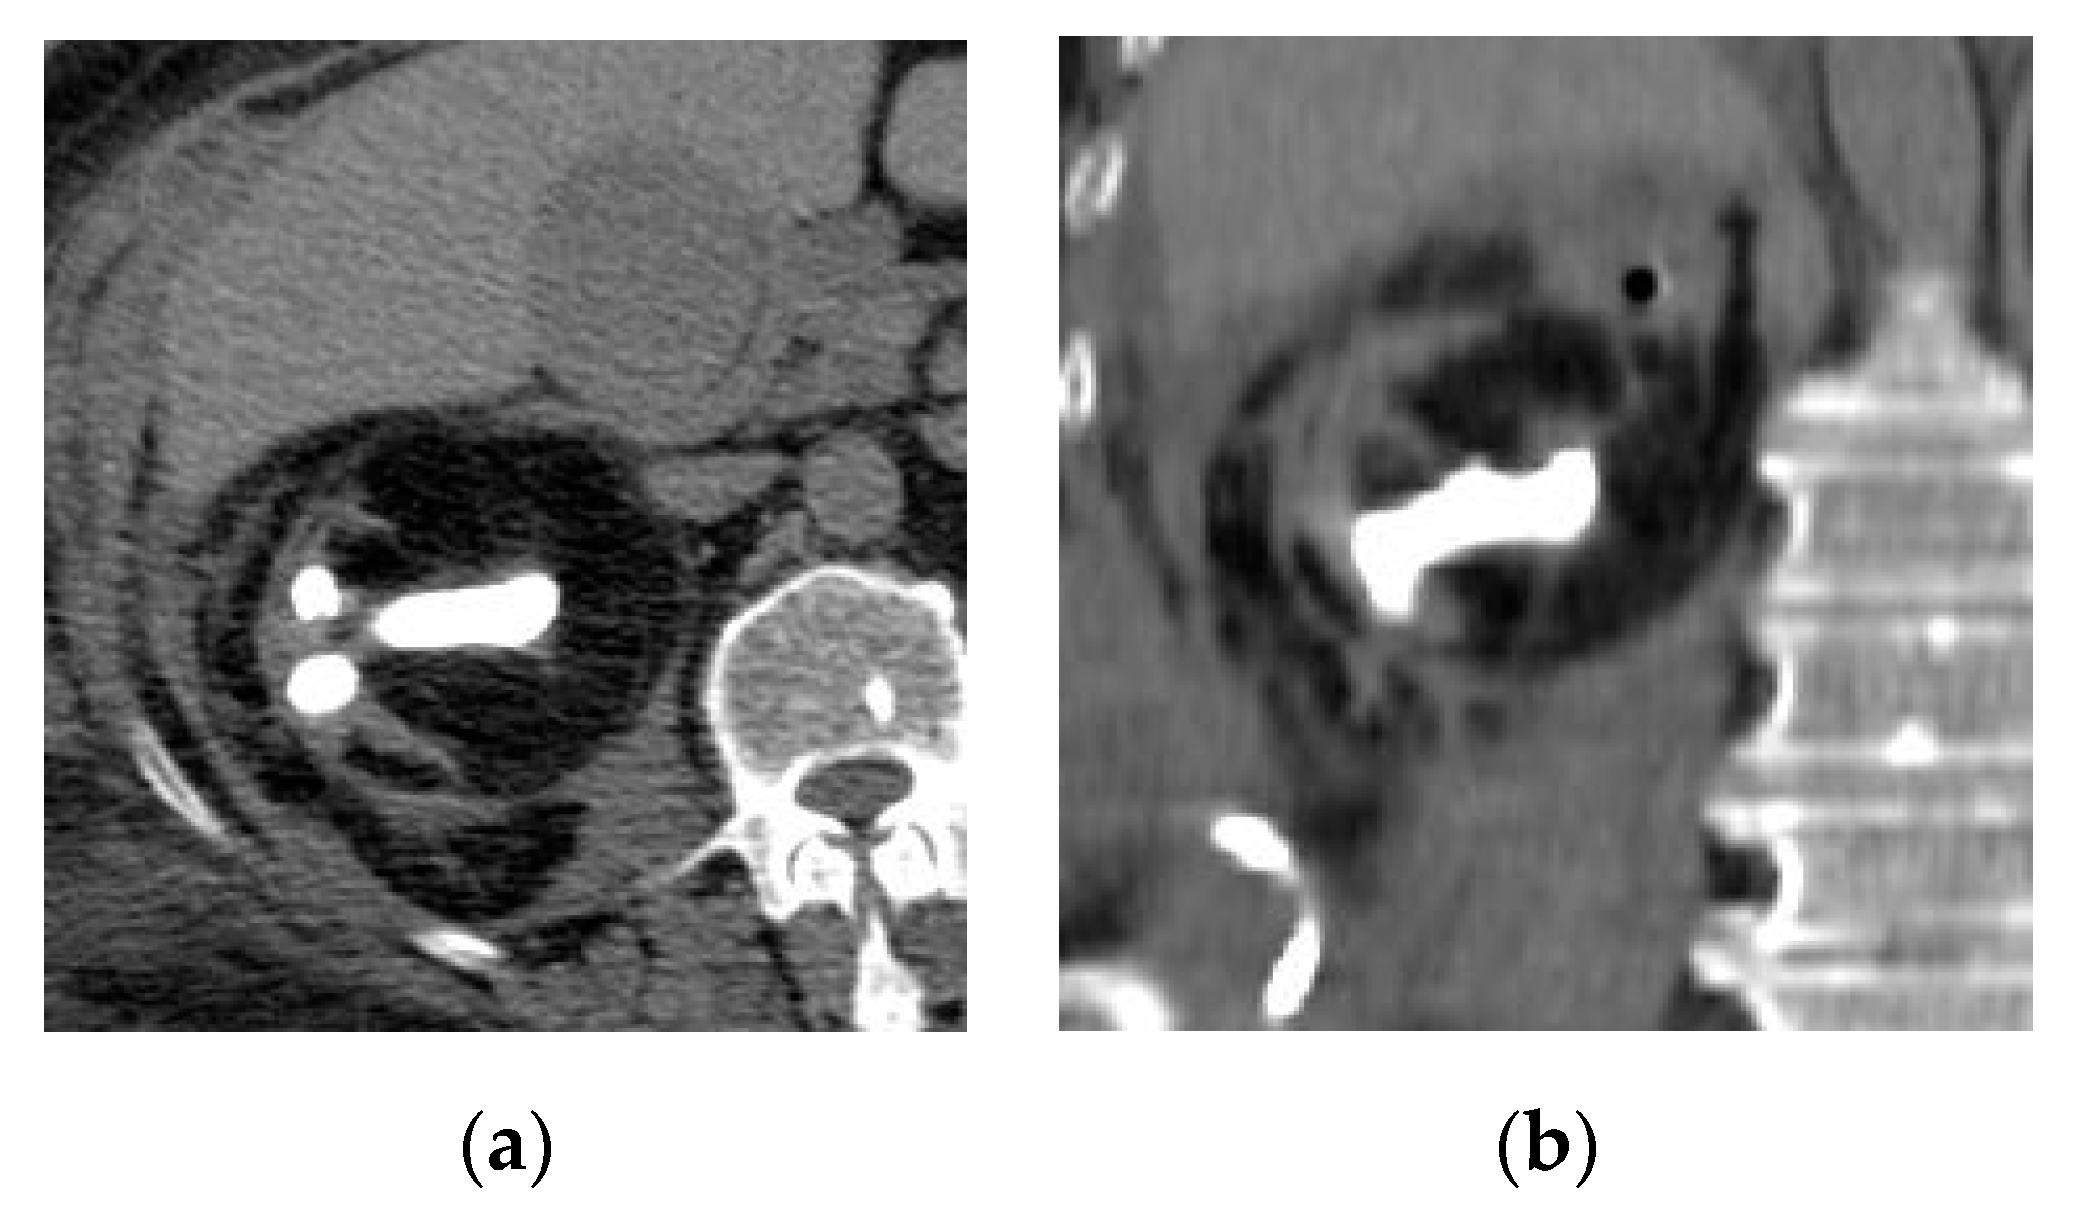

2.3. Pyonephrosis

| Pyonephrosis | Dilated thick-walled hyperenhancing collecting system, distended with high attenuation pus-filled fluid, fluid—fluid layering at T2WI, and thinning of the renal cortex. |